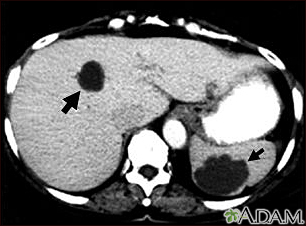

Liver and spleen cysts - CT scan